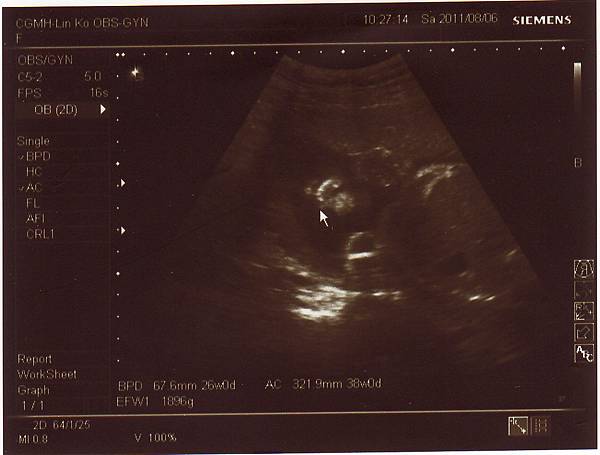

2011.08.06 26週 例行性產檢

終於今天產檢,問了醫生寶寶大小,

醫生說大約九百多克,和同期的寶寶比起來重量也不輕,

而兔妹妹的發展也符合懷孕週數,